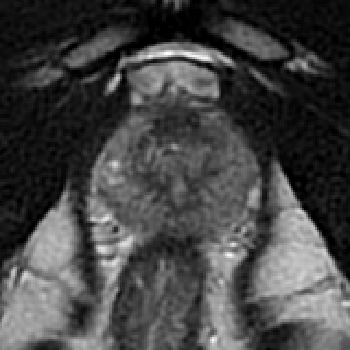

The emergence of multi-parametric magnetic resonance imaging (mpMRI) has had a profound impact on the diagnosis of prostate cancers (PCa), which is the most prevalent malignancy in males in the western world, enabling a better selection of patients for confirmation biopsy. However, analyzing these images is complex even for experts, hence opening an opportunity for computer-aided diagnosis systems to seize. This paper proposes a fully automatic system based on Deep Learning that takes a prostate mpMRI from a PCa-suspect patient and, by leveraging the Retina U-Net detection framework, locates PCa lesions, segments them, and predicts their most likely Gleason grade group (GGG). It uses 490 mpMRIs for training/validation, and 75 patients for testing from two different datasets: ProstateX and IVO (Valencia Oncology Institute Foundation). In the test set, it achieves an excellent lesion-level AUC/sensitivity/specificity for the GGG$\geq$2 significance criterion of 0.96/1.00/0.79 for the ProstateX dataset, and 0.95/1.00/0.80 for the IVO dataset. Evaluated at a patient level, the results are 0.87/1.00/0.375 in ProstateX, and 0.91/1.00/0.762 in IVO. Furthermore, on the online ProstateX grand challenge, the model obtained an AUC of 0.85 (0.87 when trained only on the ProstateX data, tying up with the original winner of the challenge). For expert comparison, IVO radiologist's PI-RADS 4 sensitivity/specificity were 0.88/0.56 at a lesion level, and 0.85/0.58 at a patient level. Additional subsystems for automatic prostate zonal segmentation and mpMRI non-rigid sequence registration were also employed to produce the final fully automated system. The code for the ProstateX-trained system has been made openly available at https://github.com/OscarPellicer/prostate_lesion_detection. We hope that this will represent a landmark for future research to use, compare and improve upon.